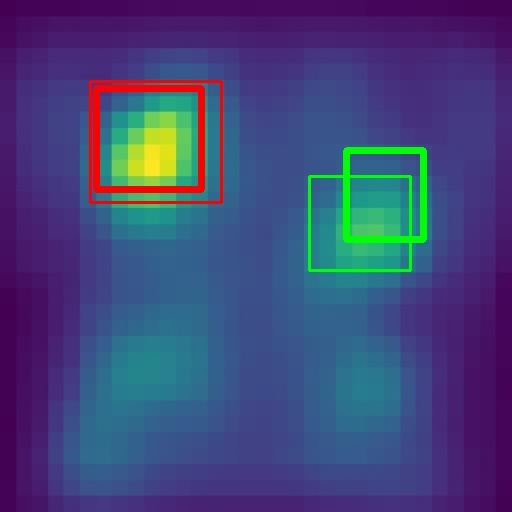

6.4 Visualization

To gain insights into the learning process of deep neural networks on CXR images, we visualize the feature map of SymFormer w/ RetinaNet at a scale of . To achieve this, we employ principal component analysis (PCA) to reduce the channels of the feature map to a single channel. The resulting single-channel map is then converted into a heat map for visualization purposes. The visualization of the learned features, along with the corresponding detection results, are presented in Fig. 6. Upon analysis, we observe that the visualization of healthy cases exhibits irregular feature patterns, indicating the absence of significant abnormalities. In contrast, the visualization of sick but non-TB cases displayed some discernible highlights, potentially representing the presence of lesions. For TB cases, the highlights in the visualization map align well with the annotated TB infection areas, thereby indicating the effectiveness of the proposed SymFormer in learning deep features for TB area detection. Furthermore, in Fig. 7, we offer qualitative comparisons between the proposed SymFormer and the baseline models for TB infection area detection. As evident, SymFormer consistently delivers superior qualitative detection results.